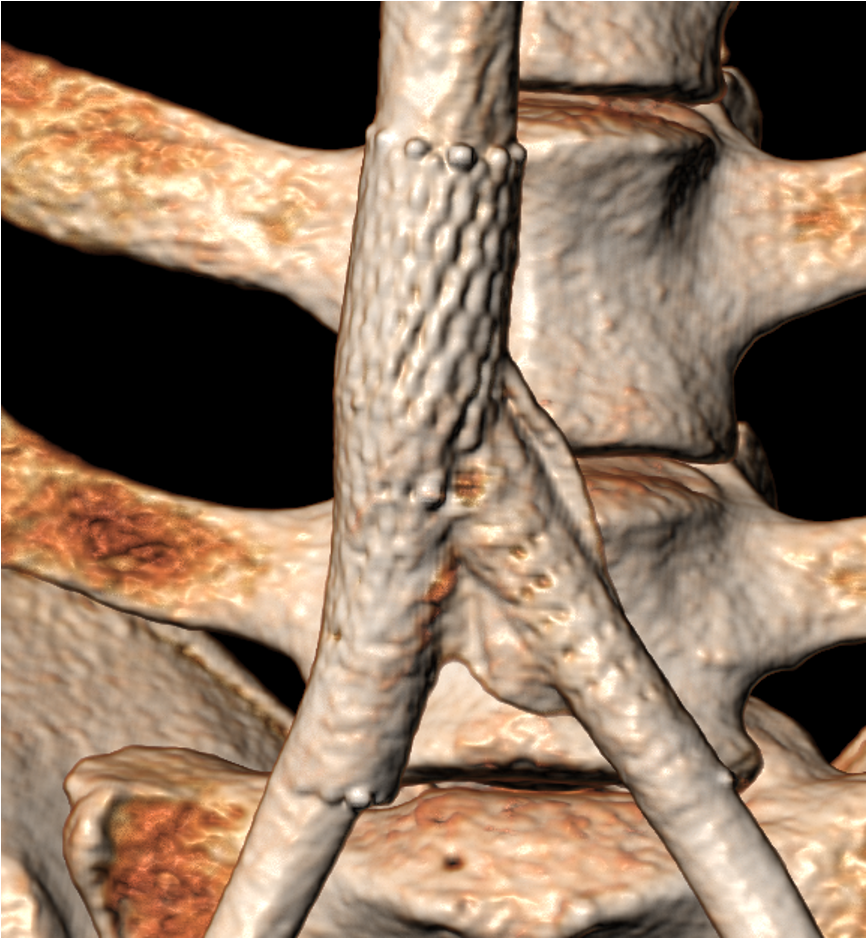

Le syndrome de Cockett, également nommé syndrome de May-Thurner, se traduit par la compression de la veine iliaque

commune gauche par l’artère iliaque commune droite contre les vertèbres lombaires.

Grâce à sa conception renforcée, la technologie T-Stent d’ID NEST s’adapte aux contraintes mécaniques de la région iliaque.

Il restaure un flux veineux continu et stable tout en épousant les variations anatomiques propres au syndrome de May-Thurner.

Sa géométrie optimisée permet une implantation précise et durable.

Le T-Stent veineux repose sur un assemblage de stents autonomes, conçus pour épouser les variations morphologiques de la veine rénale. Cette architecture modulaire assure un contact uniforme avec la paroi vasculaire, y compris en présence de compressions importantes, tout en réduisant les risques de déformation mécanique.

Les différents modules sont assemblés grâce à un système de liaison souple, capable d’accompagner les mouvements physiologiques de l’abdomen. Cette flexibilité permet de diminuer les contraintes appliquées à la veine et de maintenir une stabilité optimale face aux fluctuations de pression caractéristiques du syndrome de May-Thurner.

La conception du T-Stent garantit un ancrage solide au sein d’une région anatomique soumise à de fortes mobilités. Cette tenue renforcée permet d’éliminer le risque de migration, un facteur critique dans le traitement du syndrome de May-Thurner.

La technologie T-Stent utilise un design auto-expansible robuste permettant une apposition homogène sur la paroi veineuse.

Sa structure assure une expansion régulière et stable, indispensable pour neutraliser l’effet de compression exercé par l’artère iliaque.

Il rétablit ainsi un flux sanguin continu et réduit efficacement la stase veineuse.